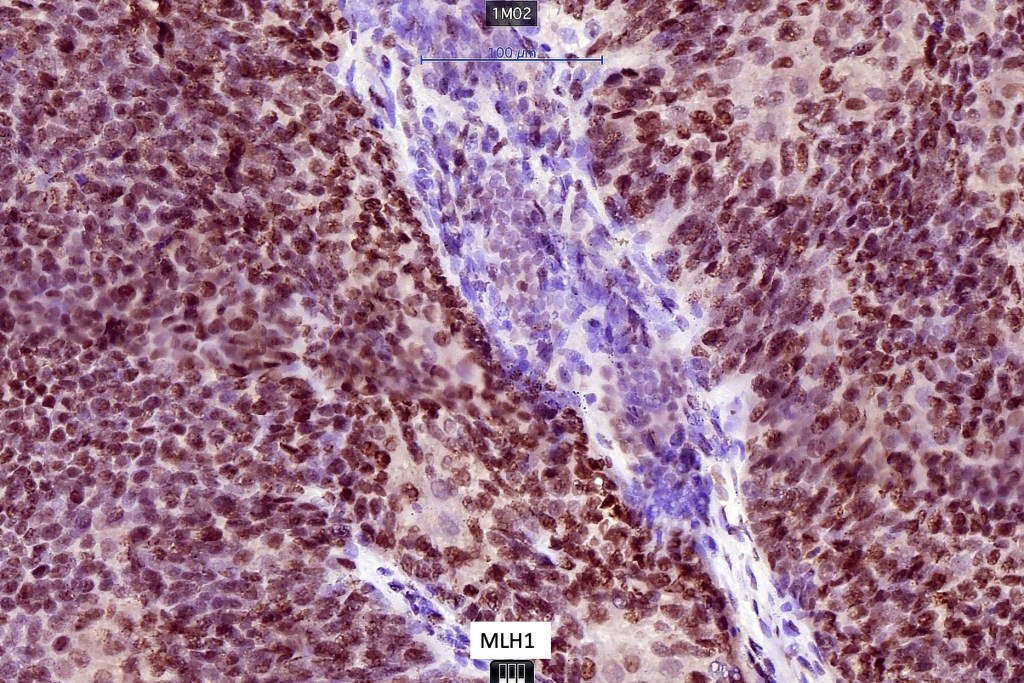

Sebaceous carcinoma from a patient with Muir-Torre syndrome kindly shared by Dr. Antonina Kalmykova.

Immunohistochemistry (from the Muir-Torre patient except for EMA which was shared by Dr. Tsheri Dorji